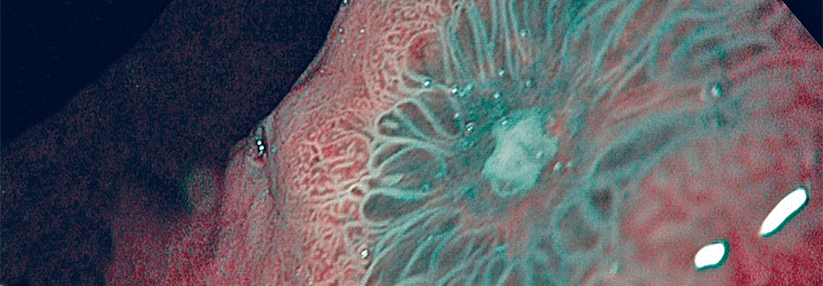

Eine Eradikation senkte das Magenkrebsrisiko um 39-73 %. Eine Eradikation senkte das Magenkrebsrisiko um 39-73 %. © SciePro – stock.adobe.com